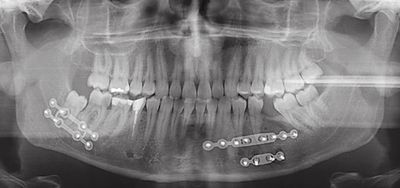

Patienten mit gebrochenen Gesichtsschädelknochen müssen wir in vielen Fällen unter Vollnarkose (Allgemeinanästhesie) operieren. Dabei werden Form, Stellung und Funktion gebrochener Knochen wiederhergestellt. Für moderne Fixierungsverfahren am Knochen verwenden wir am häufigsten miniaturisierte Titanplatten und -schrauben.

Sofern möglich nehmen wir den Eingriff durch die Mundhöhle vor, um sichtbare Narben zu vermeiden. Manchmal sind jedoch Zugänge durch die äußere Haut notwendig. In diesem Fall wählen wir kleine Zugänge in kosmetisch günstigen Regionen. Als erfahrene Mund-Kiefer-Gesichtschirurgen erzielen wir so gute ästhetische Ergebnisse.